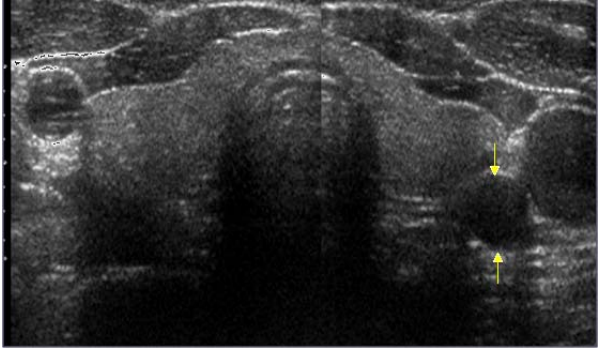

67.下圖為一健檢者之甲狀腺橫切圖,箭號所指為何?

(A)頸長肌 (B)頸動脈 (C)外頸靜脈 (D)食道